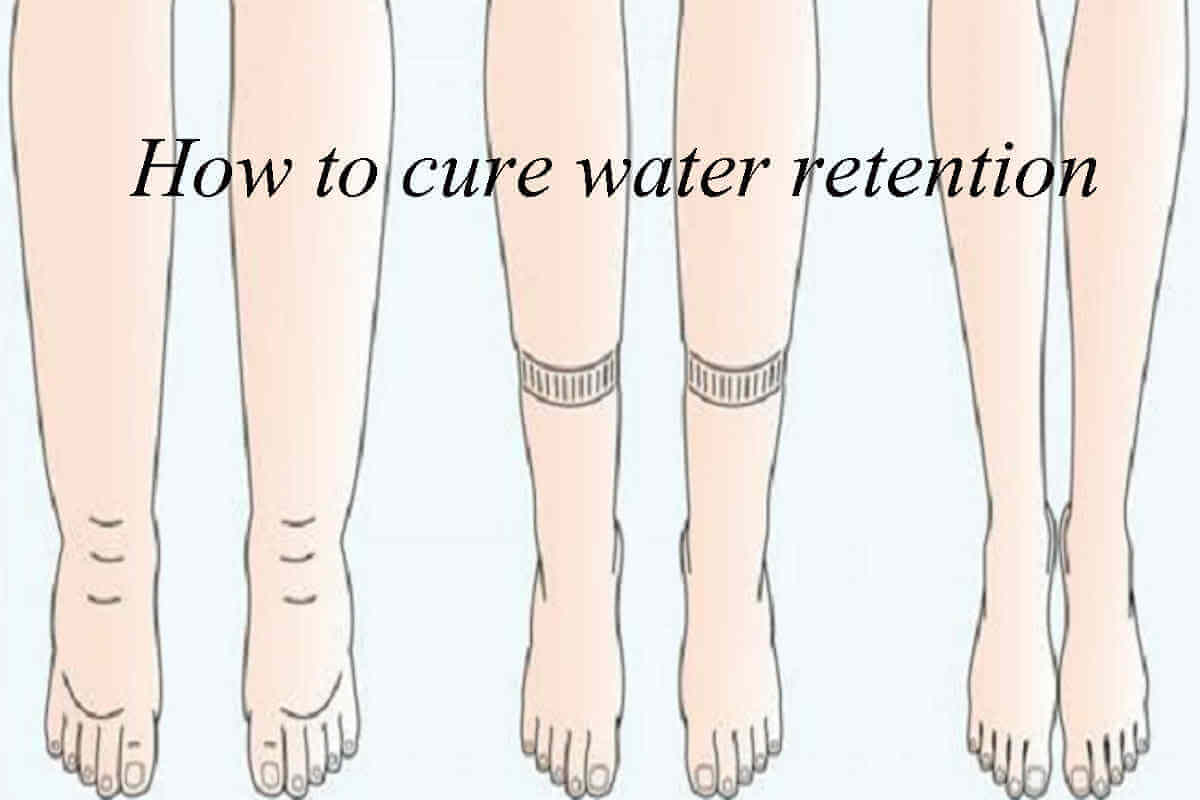

Water Retention Causes Symptoms And Remedies Possible

https://possible.in/wp-content/uploads/2020/11/cure-water-retention.jpg